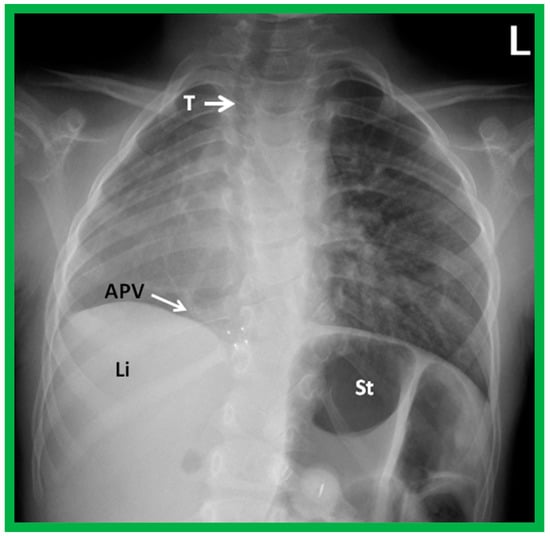

The term dextroposition is used when the heart is in the right chest, secondary to extraneous conditions. For example, the heart is pulled to the right secondary to agenesis, hypoplasia, collapse, or surgical removal of the right lung, or it is pushed towards the right by lobar emphysema, pneumothorax, pleural effusion, or diaphragmatic hernia on the left side. The cardiac apex, if it can be identified, usually points to the left. Some examples of dextroposition are shown in Figure 5, Figure 6 and Figure 7.

Figure 5. A chest roentgenogram of a child with dextroposition of the heart related to Scimitar syndrome. Hypoplastic right lung pulls the heart to the right. Note that the trachea (T) is displaced to the right, related hypoplastic right lung. An anomalous pulmonary vein (APV) is pointed out by an arrow; the name, Scimitar syndrome is derived from the sickle shape of the APV. Li, liver; St, stomach. Reproduced from reference [4].

Situs solitus is a phrase used to characterize the normal location of the visceral structures in which the liver is located on the right side of the abdomen while the stomach is on the left side (Figure 1, Figure 3, Figure 4B and Figure 5).